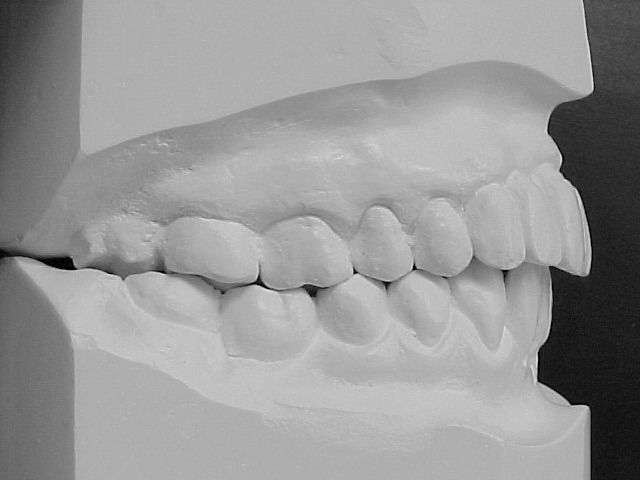

Modelos de estudo antes do tratamento

|

Modelos em gesso após o tratamento